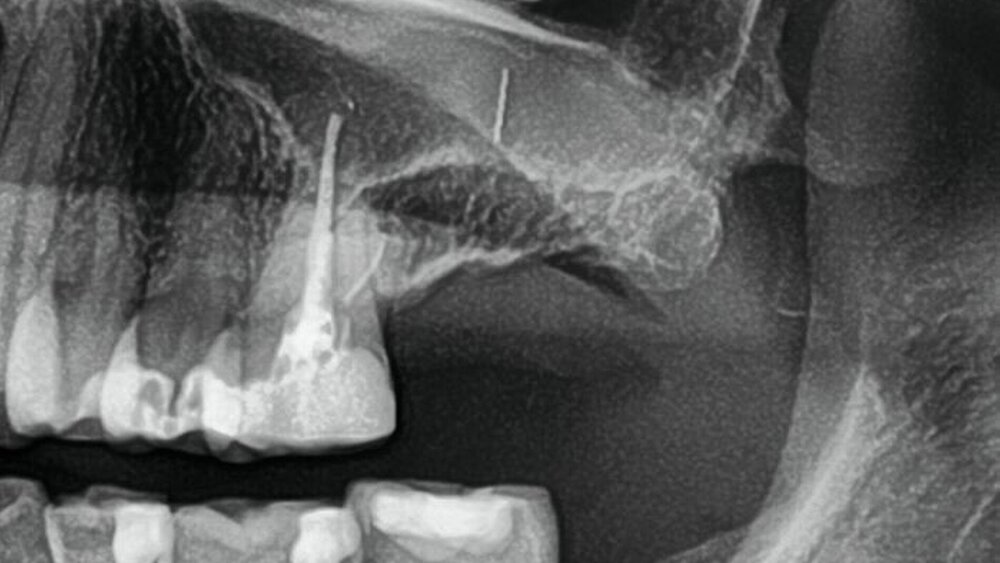

Eine Patientin stellte sich in unserer Praxis mit der Anamnese einer rezidivierenden Sinusitis der linken Kieferhöhle vor. Zum Zeitpunkt der Vorstellung war sie seit mehreren Monaten beschwerdefrei. Eine vom vorbehandelnden Zahnarzt angefertigte Orthopantomografie (OPG) zeigte jedoch einen deutlich erkennbaren Fremdkörper in der linken Kieferhöhle (Abbildung 1). Die Frau berichtete, dass die Sinusitisbeschwerden nach dem Auftreten eines Vorfalls mit einem zahnärztlichen Instrument begonnen hatten.

Nach ausführlicher Anamnese und Rücksprache mit der Vorbehandlerin stellte sich heraus, dass es sich bei dem Fremdkörper um ein frakturiertes Wurzelkanalinstrument handelte, das im Rahmen einer endodontischen Behandlung disloziert und durch den Apex in die Kieferhöhle gedrückt worden war. Die Patientin war gut informiert und wünschte die Entfernung des Fremdkörpers.